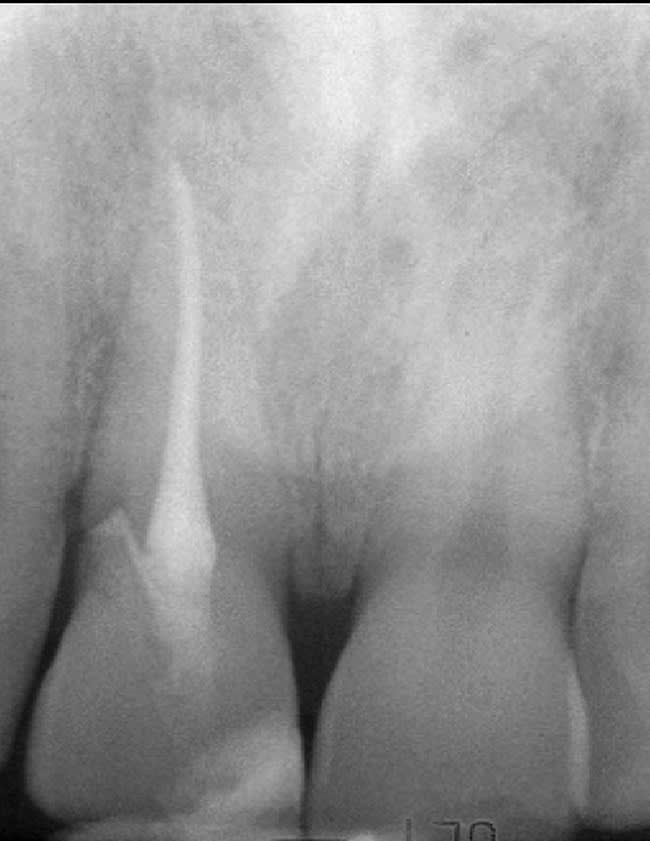

This patient presented with a non-restorable left central incisor due to external root resorption, as shown in the pre-treatment radiograph (Figure 1) and clinical photograph (Figure 2). The patient had good bone levels. The papilla positions were also good, but the cervical margins had some asymmetry with recession on the adjacent teeth. The goal was to preserve the papilla levels and the facial gingival margin level on the central incisors while also improving the gingival levels on the lateral incisors. Due to the patient’s cost concerns, the lateral incisors were not treated except for extending the CTG on the left central incisor only. A custom healing abutment was used to support the peri-cervical soft-tissue form.

This was an esthetic high-risk case due to extremely high patient expectations and existing distal papilla bone loss. The patient, who had sustained a vertical root fracture of the right central incisor during a snowboarding accident, also presented with a facial fistula at mid-root level (Figure 4 and Figure 5).